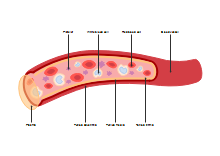

illustrazione scientifica - anatomia umana